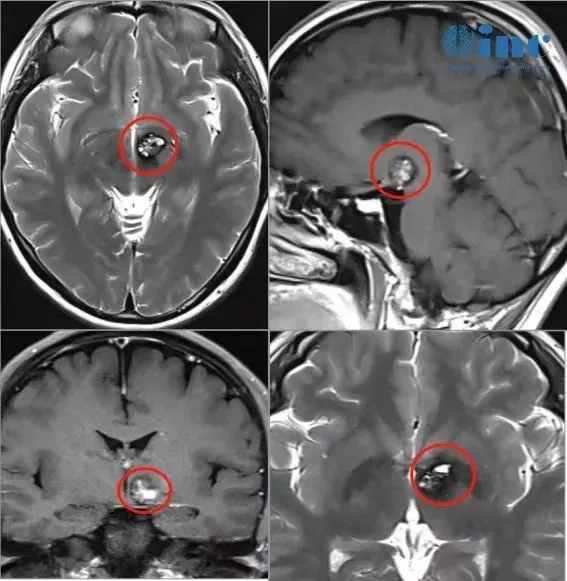

2022年3月,文文第一次察觉到身体的异常——双眼向左侧视物时总会一阵晕眩。起初她以为是过度劳累,休息几天就能缓解,可不适感反复出现。怀着忐忑的心情去医院检查后,一张“左侧基底节区海绵状血管瘤,伴少许出血”的诊断报告,像一块巨石砸懵了她。

家人带着她紧急赶往北京求医,磁共振检查提示“左侧丘脑基底节占位,海绵状血管畸形合并静脉畸形可能性大”。医生建议药物治疗,让她半年后复查。

2023年初,文文再次出现眩晕、站立不稳的症状,复查结果显示病变略有增大。可当她再次恳求手术治疗时,得到的依旧是“手术并发症风险过高,建议继续保守治疗”的回复。